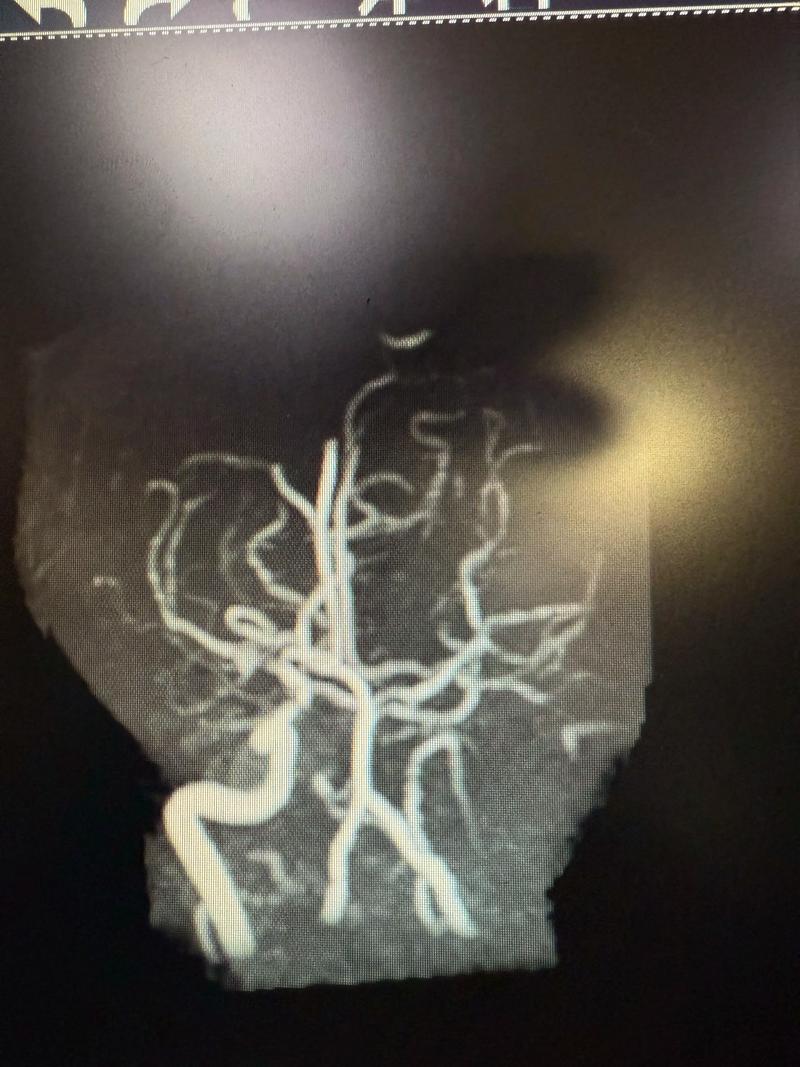

(图片来源网络,侵删)

(图片来源网络,侵删)- 可能住院 5-7天,主要目的是观察术后24-72小时内的急性期变化,确保没有出血等严重并发症,并开始进行康复训练。